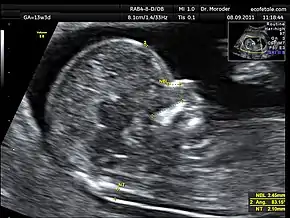

![]() Measurements of fetal nuchal translucency, nasal bone and facial angle according to the standards of the Fetal Medicine Foundation | |

A nuchal scan or nuchal translucency (NT) scan/procedure is a sonographic prenatal screening scan (ultrasound) to detect chromosomal abnormalities in a fetus, though altered extracellular matrix composition and limited lymphatic drainage can also be detected.[1]

Procedure

Nuchal scan (NT procedure) is performed between 11 and 14 weeks of gestation, because the accuracy is best in this period. The scan is obtained with the fetus in sagittal section and a neutral position of the fetal head (neither hyperflexed nor extended, either of which can influence the nuchal translucency thickness). The fetal image is enlarged to fill 75% of the screen, and the maximum thickness is measured, from leading edge to leading edge. It is important to distinguish the nuchal lucency from the underlying amniotic membrane.[8]

Normal thickness depends on the crown-rump length (CRL) of the fetus. Among those fetuses whose nuchal translucency exceeds the normal values, there is a relatively high risk of significant abnormality.